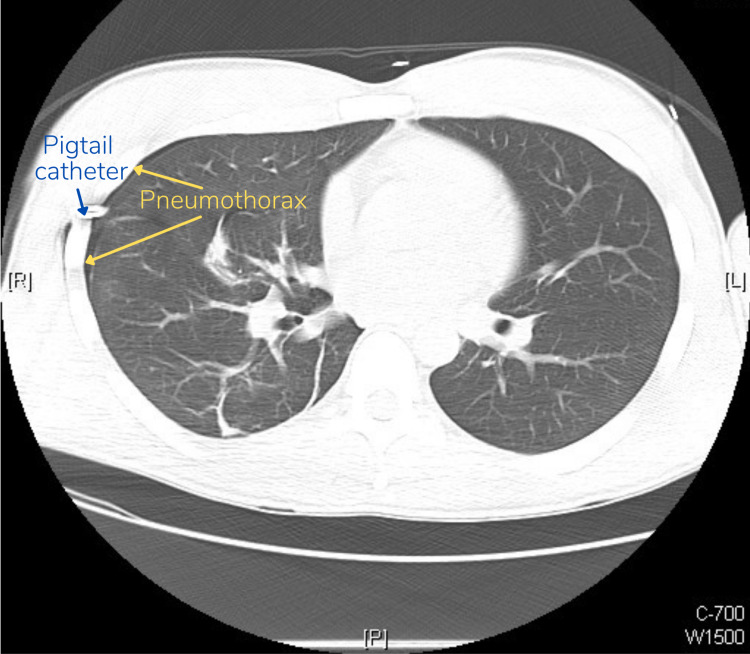

A follow-up chest CT conducted several minutes later to evaluate the lung parenchyma revealed that there was still a small (5%) residual pneumothorax in addition to blebs-small sacs of air from ruptures in the lung tissue, which likely were the cause for the patient’s SP [Figure 3].

Although not used in our patient’s case, point-of-care ultrasonography (POCUS) is another imaging modality that can be used to rapidly diagnose or rule out pneumothorax at the bedside [ref. 6]. The development of the e-FAST (extended focused assessment with sonography for trauma) protocol allows the use of POCUS to look for free intraperitoneal fluid, free fluid in the pelvis, pericardial fluid, pleural effusion, and notably, pneumothorax [ref. 7]. In a study comparing e-FAST to CXR, the e-FAST showed higher sensitivity over CXR in detecting post-traumatic pneumothoraces (48.8% versus 20.9%) [ref. 8]. CT, however, has the highest sensitivity for detecting pneumothoraces, especially when they are small, and can also reveal blebs. This is highlighted in our patient’s case, where the follow-up chest radiograph demonstrated resolution of the pneumothorax, but the CT demonstrated a small residual one. Leaving pneumothorax untreated could lead to respiratory failure and pneumomediastinum, amongst other life-threatening complications [ref. 9].